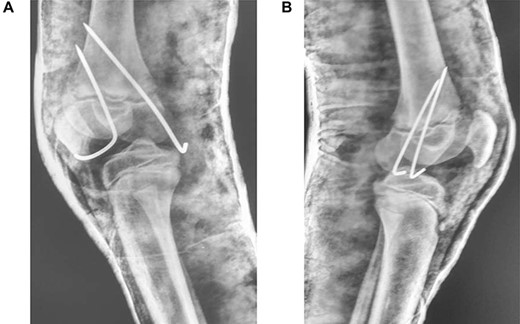

In theatre, general anaesthesia and prone positioning were performed. Closed reduction with gentle traction was achieved, followed by gradual flexion of the knee (Wilkin’s Manoeuvre). The physeal fragment was reduced with both thumbs, and reduction checked under mobile X-ray—good realignment was confirmed. Final fixation was achieved with percutaneous smooth K-wires in a cross construct (Figs 2, 3A and B). An anterior slab maintaining knee flexion was then applied. This process was repeated contralaterally. After 24 h and with adequate analgesia, bilateral foot-drop was noted. Bilateral posterior slabs were then applied.

Frontal view of both knees after closed reduction and K-wire fixation